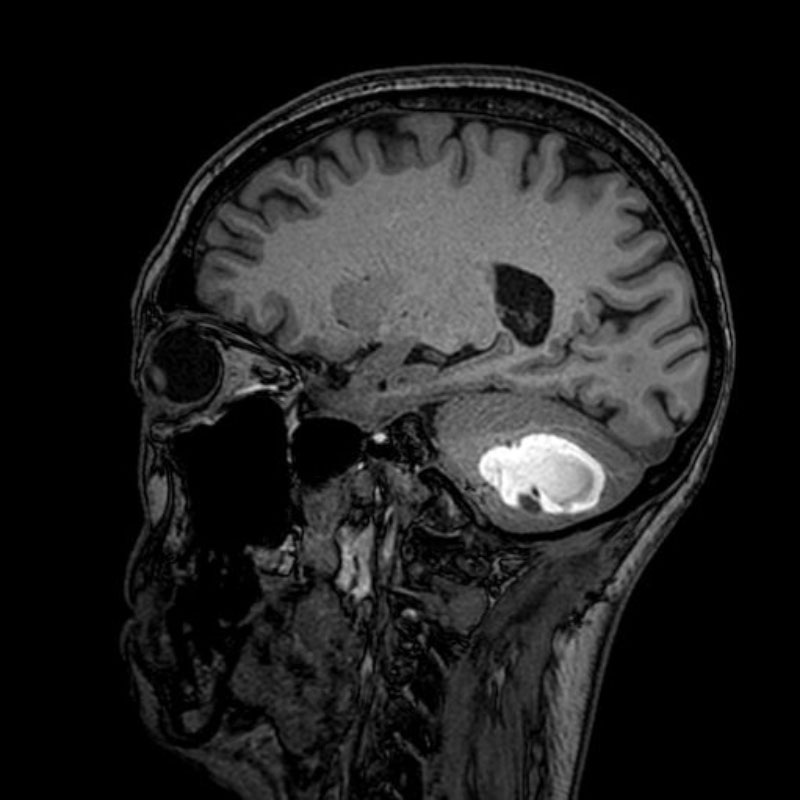

No.’25_20 手術前1

No.’25_20 手術前2